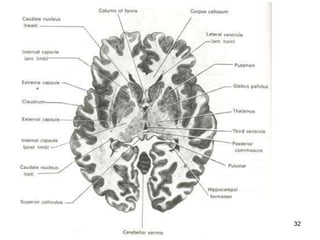

A section of the cerebrum showing some connecting nerve fibres

Basal Ganglia This area of grey matter lies deep within the cerebral hemispheres Consist of  the  caudate nucleus ,  putamen  and  globus pallidus .  They are functionally important for  controlling voluntary movements and establishing postures .  It influences skeletal muscle tone When they are altered - say in disorders like Huntington disease or Wilson disease - the person has unwanted movements, such as involuntary jerking movements of an arm or leg or spasmodic movement of facial muscles.

The  caudate   nucleus  and  putamen  along with the interposed anterior limb of the internal capsule are collectively known as the  corpus striatum  (i.e. striated body) because of their appearance.  Similarly, the shape of the  putamen  and  globus   pallidus  resembles a lens, and they are collectively called the  lenticular nucleus .

A section ofthe cerebrum showing some connecting nerve fibres

Basal Ganglia Thisarea of grey matter lies deep within the cerebral hemispheres Consist of the caudate nucleus , putamen and globus pallidus . They are functionally important for controlling voluntary movements and establishing postures . It influences skeletal muscle tone When they are altered - say in disorders like Huntington disease or Wilson disease - the person has unwanted movements, such as involuntary jerking movements of an arm or leg or spasmodic movement of facial muscles.